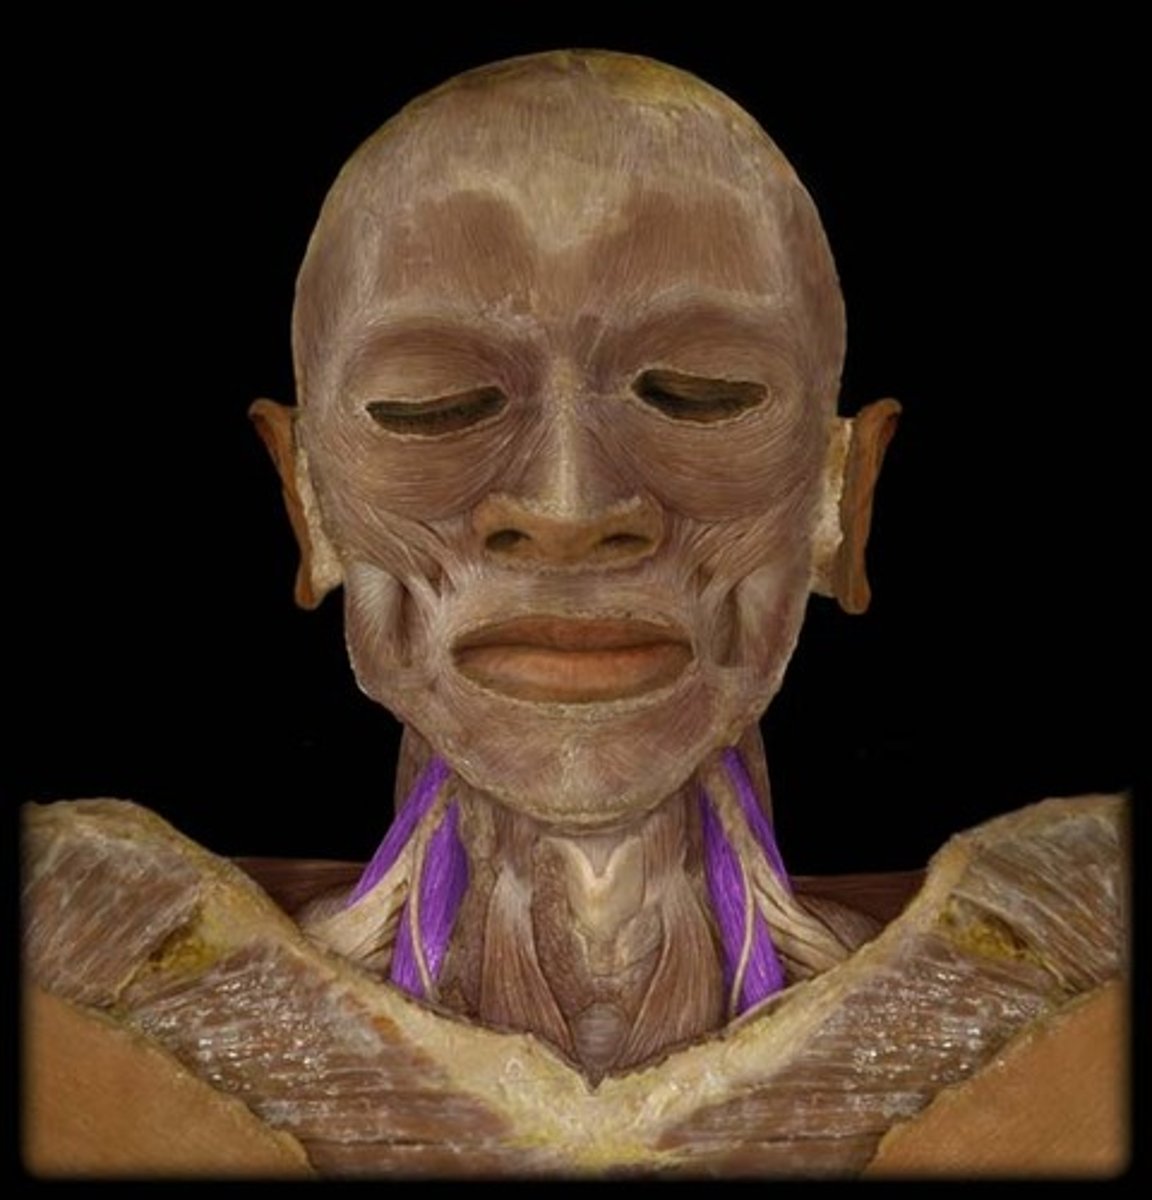

Platysma

Origin: Fascia of deltoid and pectoralis major

Insertion: Mandible, skin and subcutaenous tissue of lower face

Action: depresses mandible, draws angle of mouth downward (pout), tightens skin of the neck

Sternocleidomastoid

Origin: Manubrium of sternum; medial 1/3 of clavicle

Insertion: Mastoid process of temporal bone

Action: head tilt, rotating head

Scalene

Origin: Transverse process of all cervical vertebrae

Insertion: Ribs 1-2

Action: helps breathe by elevating upper ribs, flexes head, rotates head side to side